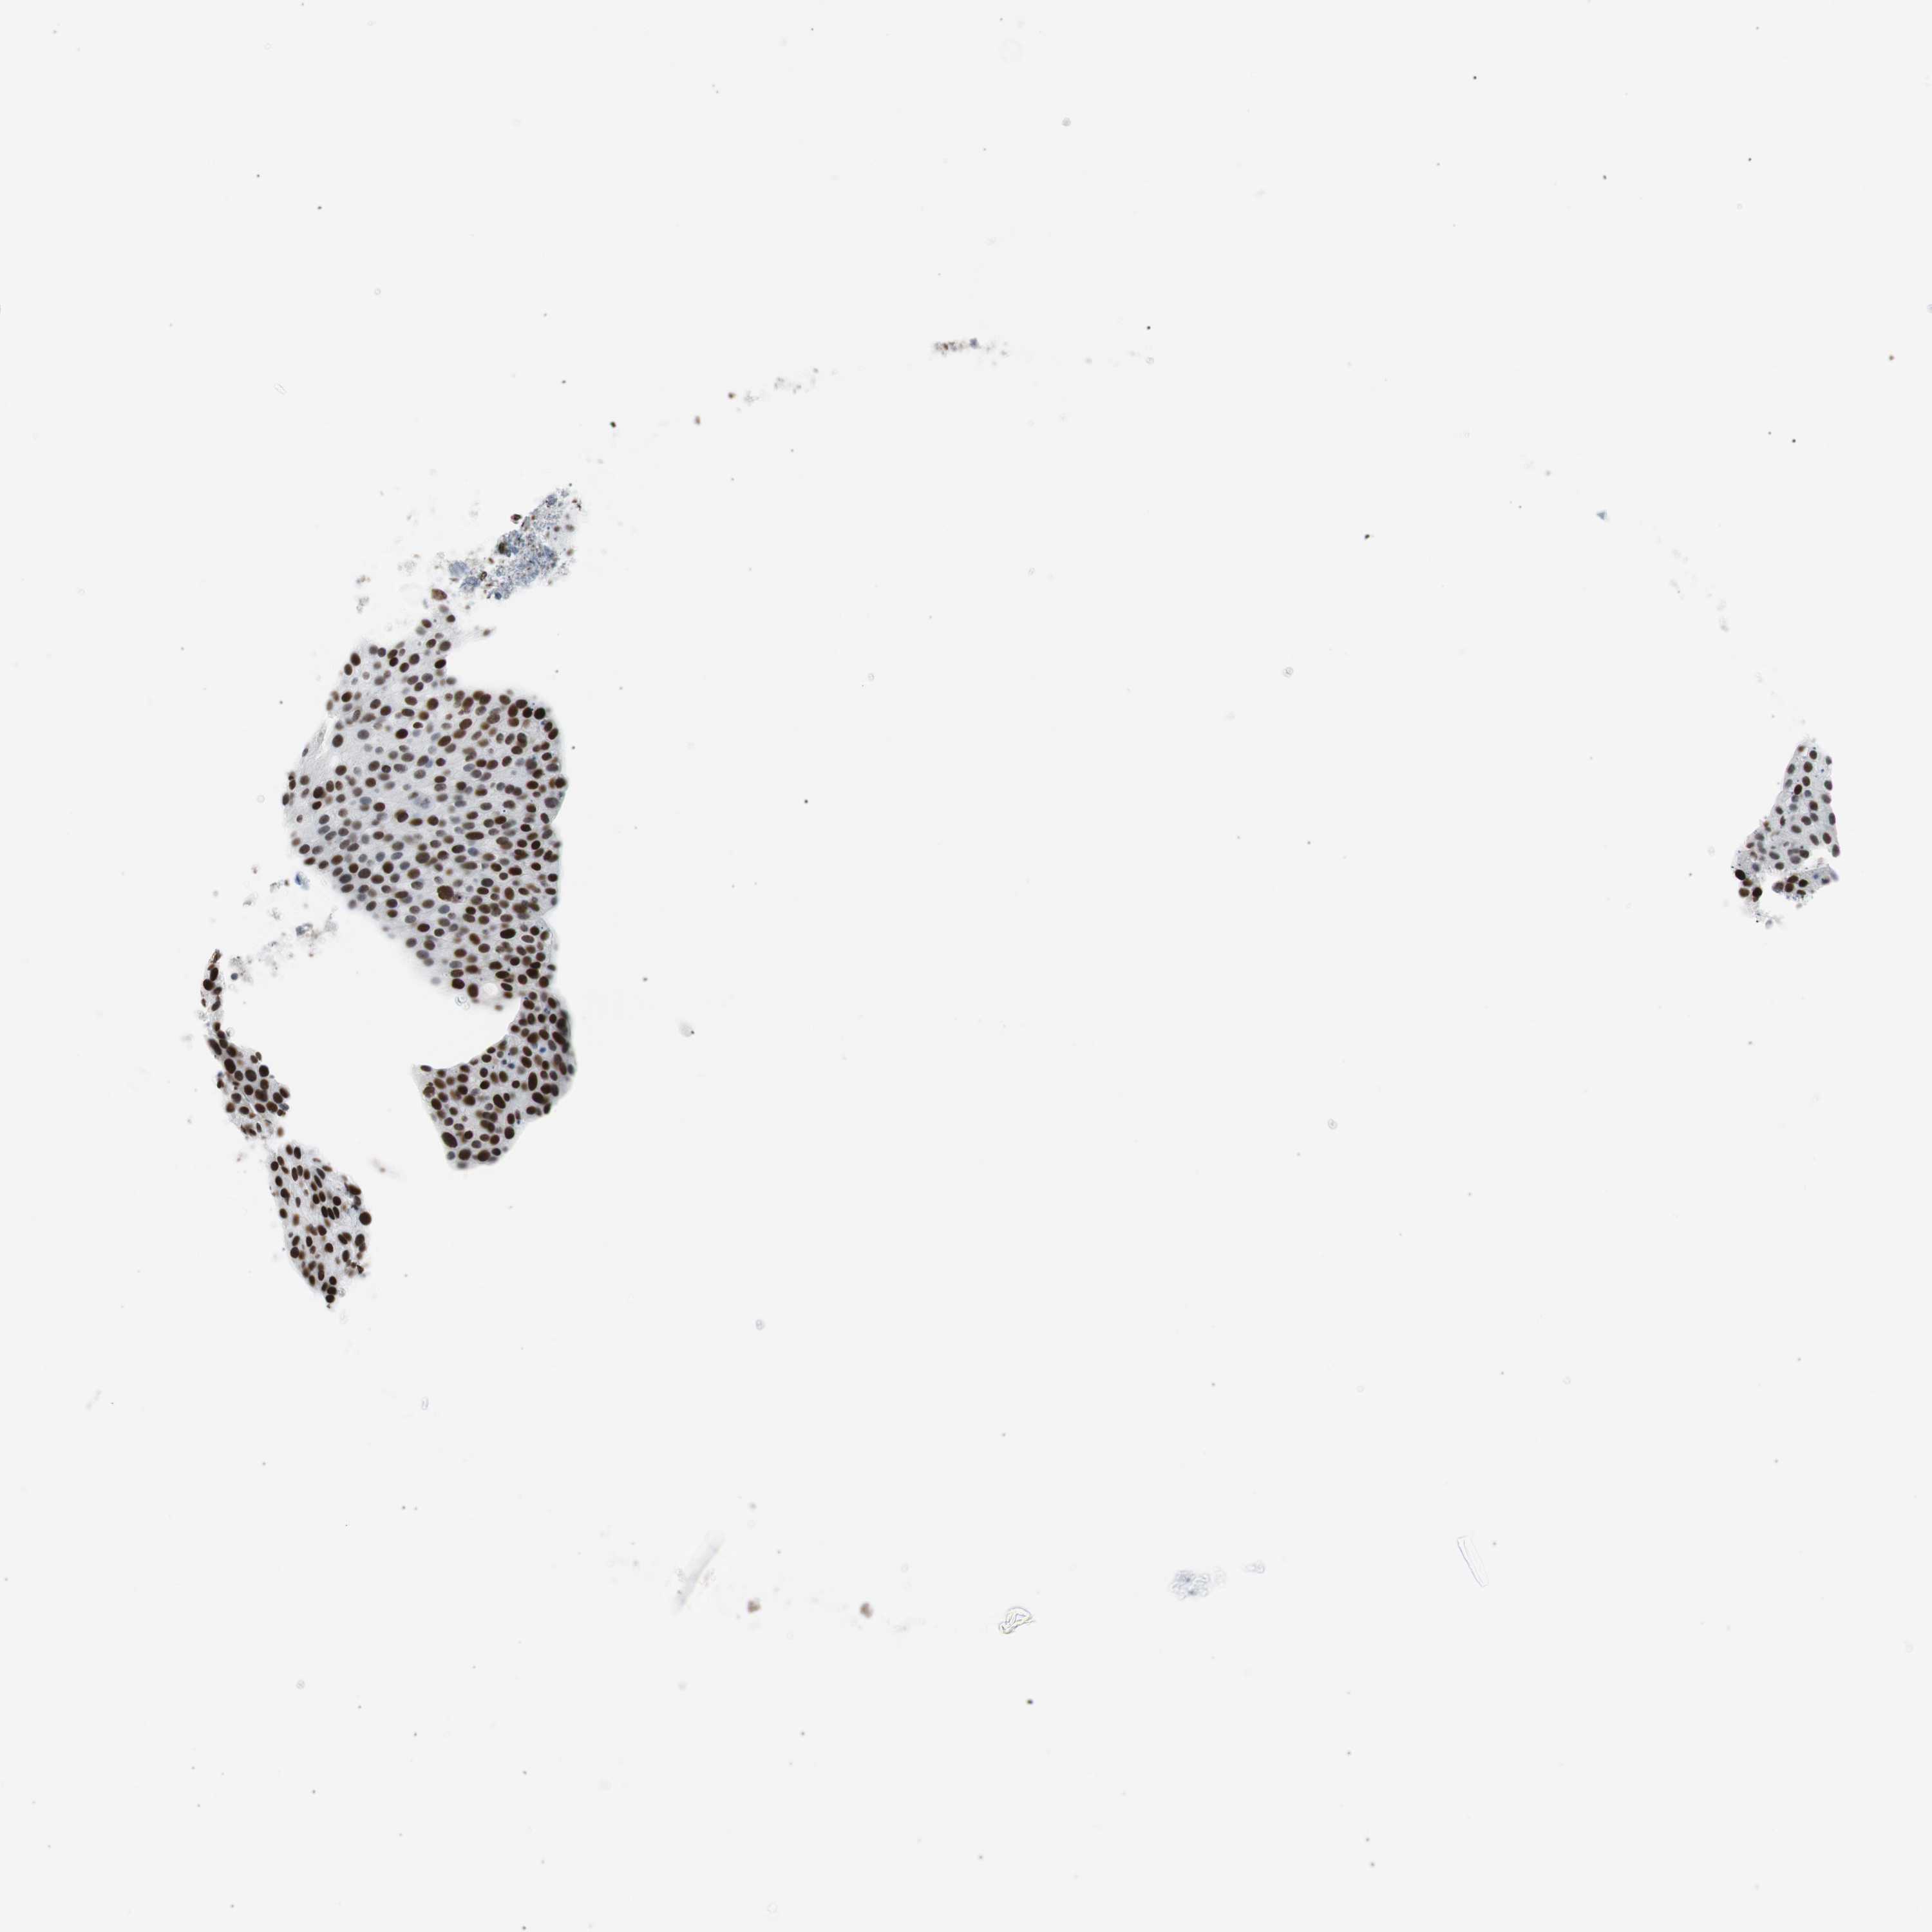

UROTHELIAL CANCER - Protein expressioni

A mouse-over function shows sample information and annotation data. Click on an image to view it in a full screen mode. Samples can be filtered based on level of antibody staining by selecting one or several of the following categories: high, medium, low and not detected. The assay and annotation is described here.

Antibody stainingi

Antibody staining in the annotated cell types in the current human tissue is reported as not detected, low, medium, or high, based on conventional immunohistochemistry profiling in selected tissues. This score is based on the combination of the staining intensity and fraction of stained cells.

Each image is clickable and will lead to virtual microscopy that enables deeper exploration of all samples and also displays staining intensity scores, fraction scores and subcellular localization as well as patient and tissue information for each sample.

Antibody CAB004213

Staining

High

Medium

Low

Not detected

Intensity

Strong

Moderate

Weak

Negative

Quantity

>75%

75%-25%

<25%

None

Location

Nuclear

Cytoplasmic/membranous

Cytoplasmic/membranous,nuclear

Urothelial carcinoma, Low grade

Urothelial carcinoma, High grade